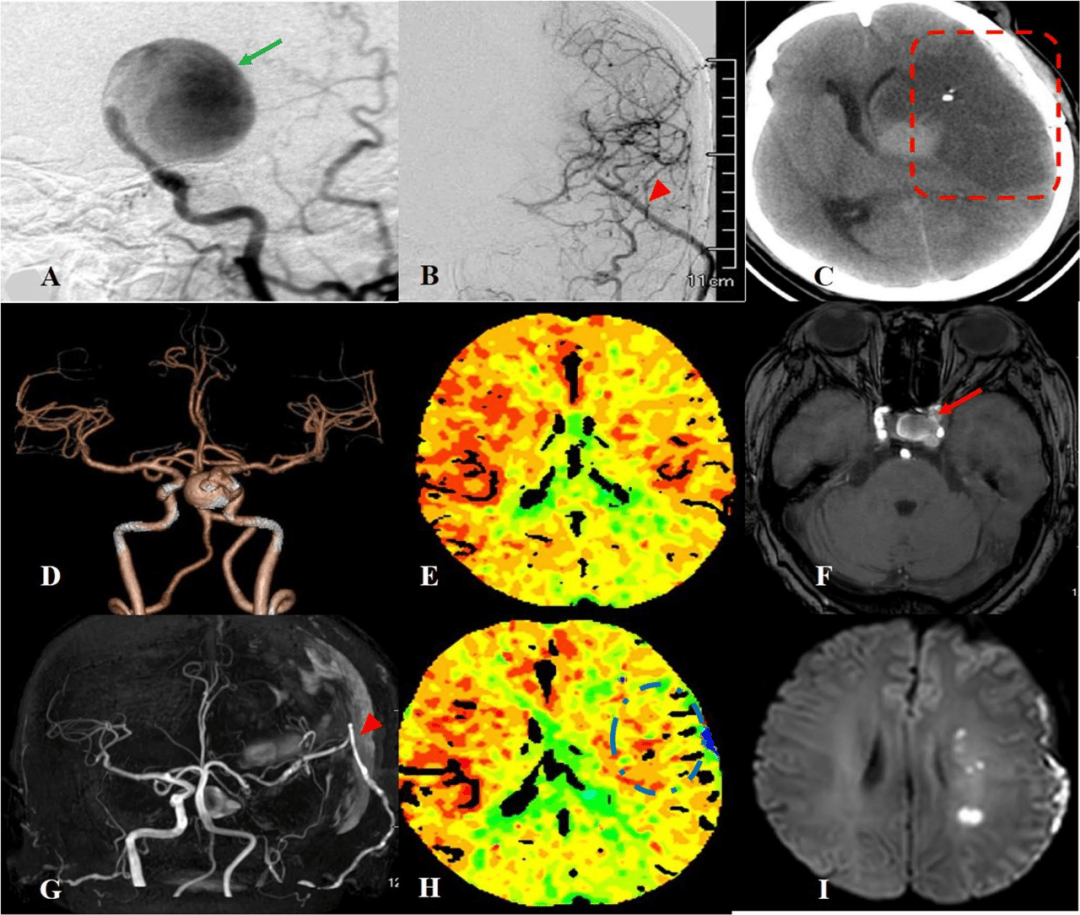

颅内动脉瘤夹闭手术 写美篇患者陈某,女,54岁,以突发头痛入院,头颅ct